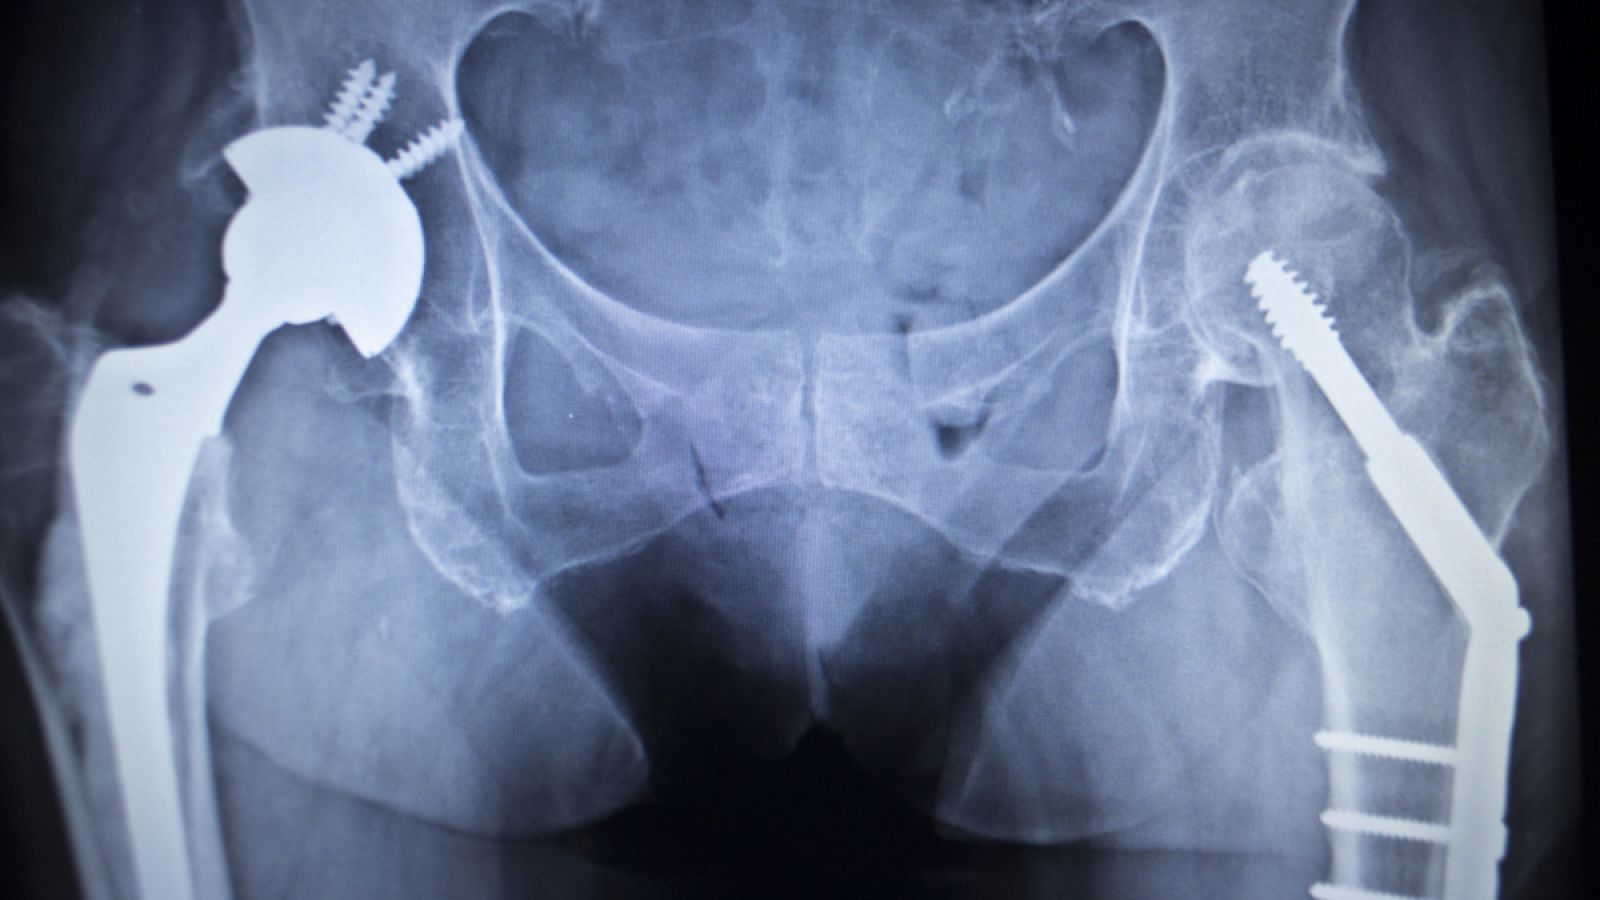

Con esta nueva tecnología pueden ser tratadas distintas aleaciones de uso médico, como por ejemplo implantes de titanio para sustituir tejido óseo, implantes dentales, implantes para cirugía maxilofacial y de la columna vertebral y prótesis de articulaciones, es decir, implantes que se someten a grandes cargas mecánicas.